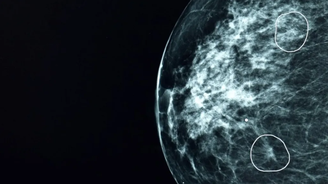

Duas áreas de preocupação destacadas por ferramenta de IA

Uma ferramenta de inteligência artificial testada pelo NHS, o serviço público de saúde do Reino Unido, identificou com sucesso pequenos sinais de câncer de mama que não haviam sido detectados por médicos.

A ferramenta, chamada Mia, foi testada em conjunto com médicos do NHS e analisou mamografias de mais de 10 mil mulheres.

Na maioria dos exames, Mia não identificou indícios de câncer, mas sinalizou com sucesso todos aqueles em que havia indícios apontados por médicos antes, além de outros 11 em que os médicos não haviam identificado tumores.